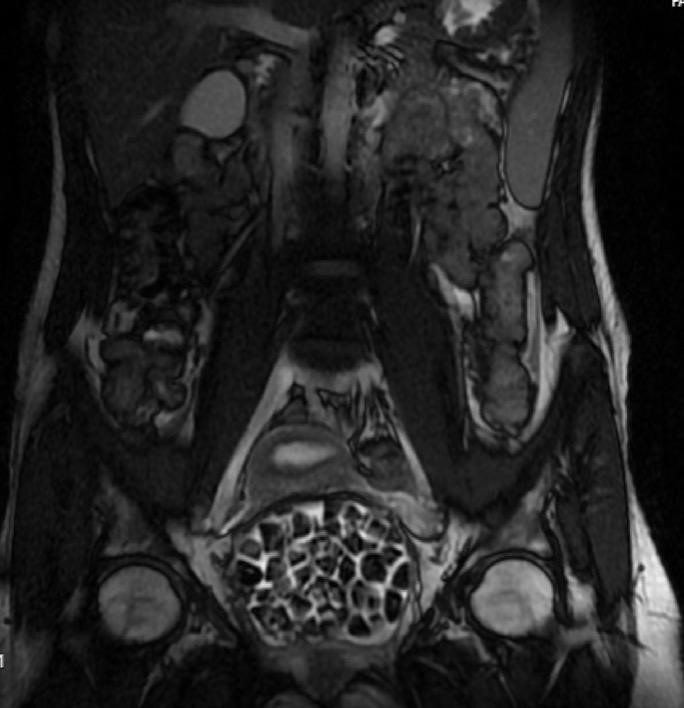

Hastasının durumuna yönelik konuşan Üroloji Uzmanı Doç. Dr. Erkan Erkan "Hastamızın 2004 yılında doğduğunu ardından doğar doğmaz ekstrofi vezika dediğimiz 50 binde bir görülen bir anomaliden dolayı art arda ameliyatlar geçirdiğini öğrendik. 10 yaşında yine bir ameliyat geçirmişti, gerekli görüntüleme ve tetkiklerimizi yaptırdık. Normalde mesanesinin olması gereken yerin hemen arka kısmında taşlarla dolu bir kese olduğunu gördük, bunun üzerine ek görüntülemeler; MR çektirdik. Hastamız çelişkili açıklamalar almıştı, kendi radyolojik kliniğimiz ve edindiğimiz konsültasyonlarda taşların mesanede değil vajinal boşlukta oluştuğunu düşündük, bir planlama yaptık. Kadın doğum hocamızın da çabasıyla taşları tamamen temizledik ardından ileride normal bir hayat sürmesi bakımından oraya plastik cerrahi yaptık. 287 adet taş çıkardık, pratikte gerçekten görünce çok şaşırdık çünkü bu aynı zamanda literatürde çok nadir görülen bir olay. Biz ameliyata hazırlanırken de teorik olarak biraz araştırdık. Literatürde gördüğümüz kadarıyla buna benzer bu tanıma uyan bir vaka vardı. Literatürde sanırım yayınlanmış 2’nci vaka olacak. Farkındalık çok önemli, bilinçli bir hastamız vardı. Doğumsal anomaliyle doğan çocuklarımızda ileride bunlara bağlı bazı sıkıntılar çıkabileceğinin öngörülmesi lazım. İlgili tedavilerini alsalar bile düzenli takiplere gelmeleri gerekiyor. İleride eğer dikkat etmezse ki zannetmiyorum, tekrarlayabilir. Bu rahatsızlık ekstrofi vezikal epispadias durumu çok nadir bir durum" dedi.

Genç kızın uzun süredir devam eden karın ağrısı olduğunu söyleyerek sözlerine başlayan Jinekolojik Onkoloji Uzmanı Op. Dr. Emin Erhan Dönmez "Mesane taşları olduğu düşünülerek daha büyük bir hastaneye refere edilmiş. Aramızda mini bir konsey yaparak muayene ettik. Vajen bir hazne görevi görerek orada durağan bir idrar, uzun süre beklediği için idrar içindeki minerallerde çökerek taşlar oluşmuş. Mesanedeki idrarın vajene akmış olabileceği ve vajende göllenen idrar nedeniyle taşların burada oluşacağını düşündük, ameliyatımızı planladık. Ameliyata tanı amaçlı girmiştik, sistoskopi (Mesane gibi idrar yollarını kapsayan kısımlardaki rahatsızlıkların teşhis ve tedavisinde kullanılan endoskopik bir yöntem) dediğimiz ameliyatı Erkan Hocam ile birlikte gerçekleştirdik. Önce mesaneyi bir görüntüledik, mesane tabanına yaklaşık 2-3 cm’lik bir alandan vajene fistülize olduğunu gördük. Mesaneden vajene geçtiğimiz esnada tüm vajenin taşlarla dolu olduğunu gördük. Tanı amacıyla girdiğimiz ameliyatta her şey de olağan gittiği için tedaviye geçtik. Taşların çıkabileceği kadar bir genişlik sağladık. Daha sonra yaklaşık en büyüğü 2,5 cm boyutlarında olan, irili ufaklı 287 tane taşı ameliyat esnasında çıkarmış olduk. Taşların tekrarlamaması için idrarın göllenmemesi, en azından dışarıya rahatça boşalabilmesi için vajinal rekonstrüksiyonu sağladık. Ameliyatta da herhangi bir problem yaşamadık. Literatürü Erkan Hocam ile birlikte değerlendirmiştik. Primer olarak vajende birikmiş olan bu kadar çok sayıda taşla ilgili bir makale görmedik, rastlamadık" dedi.